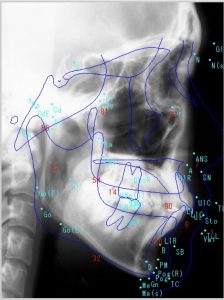

【セファロ分析から何が分かるの?】

セファロレントゲン上で、様々な角度や長さを計測し、正常な場合の数値と比較していきます。

◉骨の分析1

頭の骨に対して、上顎/下顎が大きいor小さいのかを調べます。成長し過ぎているのか、もしくは成長が足りてないのかを分析します。

◉骨の分析2

上顎骨と下顎骨の関係を調べます。

例えば、上顎に対して下顎の位置が前にある(受け口)のか?それとも後ろに引っ込んでいるのか(相対的に出っ歯に見える)が分かります。

◉歯の傾きの分析

前歯が平均と比べて、前に傾いているのかor内側に倒れているのか角度を測ります。

◉矯正治療の難易度

下顎の骨の形や、角度を計測することで矯正治療の難易度の目安を出すことができます。